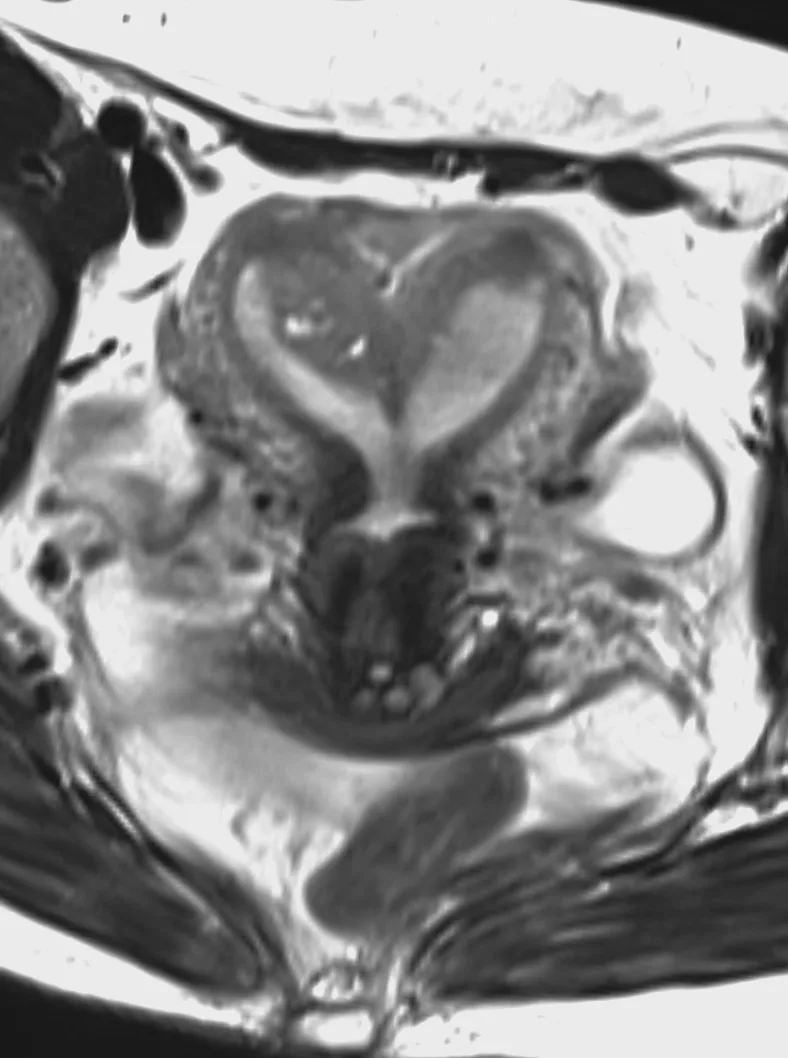

Клинический случай кавернозной мальформации, ассоциированной с венозной аномалией развития (ВАР). Следует напомнить, что ВАР часто сочетаются с каверномами, однако точные статистические данные не привожу, чтобы простимулировать самостоятельный поиск информации и закрепление знаний. Клиническая симптоматика у данного пациента отсутствует, что является типичным сценарием для подобных находок. Диагноз установлен случайно.